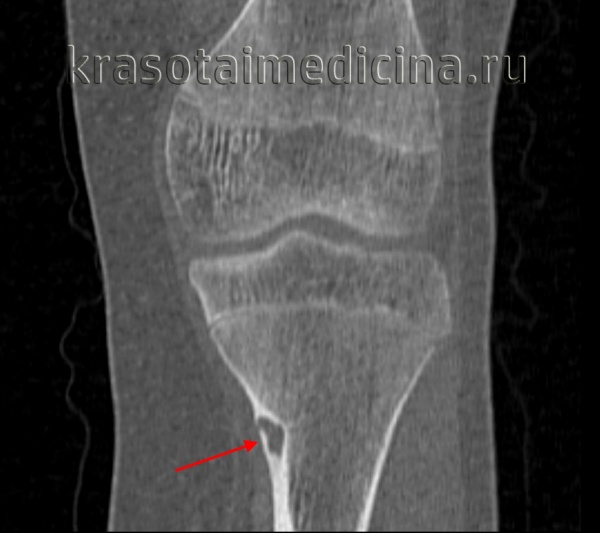

- Рентгенография кости. На снимках визуализируется кистообразные изменения или неоплазия в виде «мыльных пузырей» в метафизарной зоне. Признаки общего остеопороза отсутствуют, вокруг измененного участка может просматриваться остеосклероз. Границы доброкачественной ГКО более четкие, но из-за местно-агрессивного роста при значительном размере возможно появление «костного козырька». Выраженная периостальная реакция нехарактерна. Злокачественная остеокластома имеет нечеткую структуру. На снимках рано обнаруживается разрушение кортикального слоя.

- КТ и МРТ кости. Компьютерная томография дает более четкое представление о форме, размерах, границах гигантоклеточной опухоли, в сомнительных случаях позволяет подтвердить или опровергнуть разрыв коркового слоя. В ходе магнитно-резонансной томографии исследуют интрамедуллярный и кистозный компоненты, оценивают состояние окружающих мягких тканей, расположение сосудов и нервов. Методики помогают выбрать оптимальный вариант хирургического вмешательства, спланировать операцию.